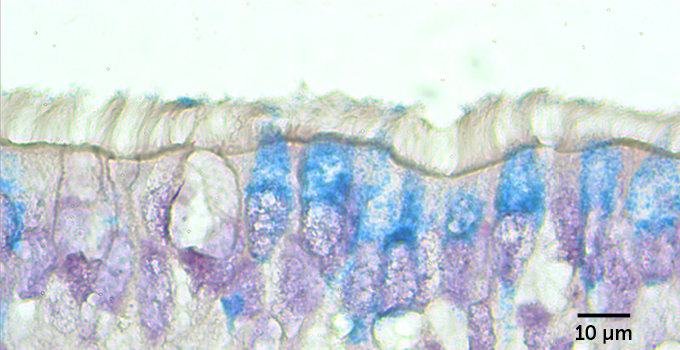

But not all the cells in the infected lawn were affected equally. Looking at the cells from the side, researchers could see that cells sporting cilia were infected with the coronavirus. But mucus-producing cells called goblet cells, which don’t have cilia, were rarely infected. That may be because a protein called ACE2 decorates the surface of ciliated cells far more often than it does goblet cells. ACE2 is the protein that the coronavirus uses as a door into cells.

All that extra mucus from the treated cells could ensnare viruses and expel them from the lungs before much damage is done. But people with nonallergic asthma and COPD make plenty of mucus too, and they aren’t protected from the virus. So Ehre and colleagues stripped away the mucus to see how the airway cells fared without this phlegmy trap.